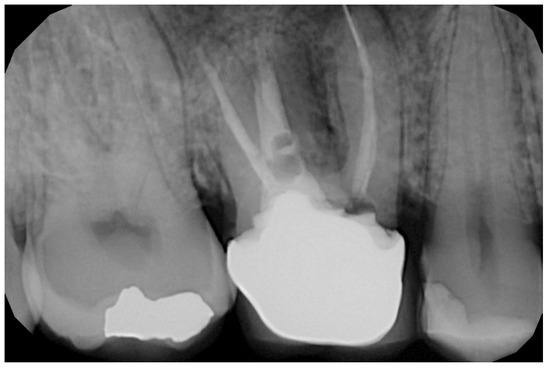

2.6. Case Presentation. Nano-HA Applied to Socket Preservation Procedures

3. Results